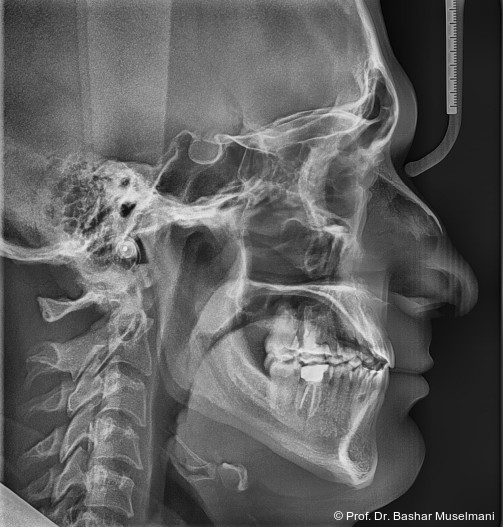

Fernröntgenologische Befunde (Behandlungsbeginn)

• SNA: 81,5°

• SNB: 84,3°

• ANB: −4,9°

• Wits-Wert: −8,4 mm

Die Abbildungen 1 bis 3 zeigen die initiale klinische und radiologische Ausgangssituation.

Während des Behandlungsverlaufs wurden ein Kontroll-Fernröntgenseitenbild sowie ein Orthopantomogramm angefertigt.

Fernröntgenologische Befunde (Zwischenkontrolle)

• SNA: 81,9°

• SNB: 83,9°

• ANB: −2,1°

• Wits-Wert: −2,0 mm

Fernröntgenologische Befunde

Initial

• ANB: −2,9°

Zwischen

Ende

• SNA: 82,0°

• SNB: 81,5°

• ANB: 0,6°

• Wits-Wert: +0,7 mm

Zusammenfassung der sagittalen Veränderungen

• SNA (maxillare Position): leichte Zunahme von 81,5° auf 82,0° → maxillare Position blieb nahezu stabil.

• SNB (mandibuläre Position): Abnahme von 84,3° auf 81,5° → retrusive Tendenz des Unterkiefers.

• ANB (Relation Ober- zu Unterkiefer): Zunahme von −2,9° auf 0,6° → deutliche Korrektur der Klasse III-Relation hin zu neutraler Okklusion.

• Wits-Wert: Verbesserung von −8,4 mm auf +1,7 mm → klinisch stabile sagittale Okklusion erreicht.

Interpretation

Die Behandlung führte zu einer signifikanten Korrektur der Klasse III-Fehlstellung durch retrusive Unterkieferposition und leichte Anpassung der Maxilla, was in einer nahezu normalen sagittalen Kieferrelation resultierte.